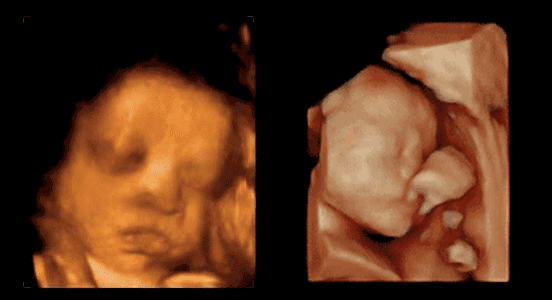

煊光(guāng)四維彩超E10是目前世界先進的四維彩色超聲

是産前超聲技術(shù)權威

卓越的胎兒排畸檢查

NT檢查評估早孕期胎兒染色體(tǐ)異常的風(fēng)險,中孕期胎兒畸形進行評估

堪比IMAX的高清畫(huà)質,成像效果驚人(rén)

能看(kàn)到皺眉、微笑(xiào)、打哈欠、吸吮和吞咽、小腿交叉盤坐(zuò)等